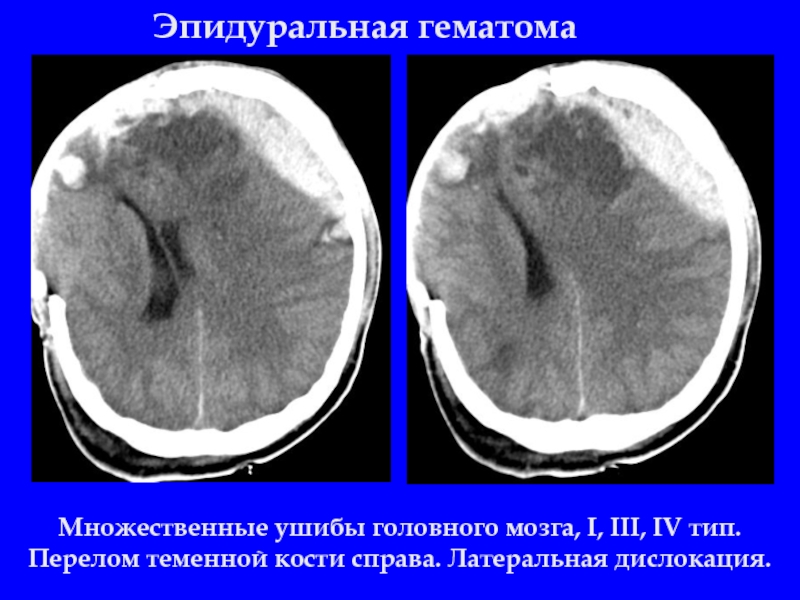

Слайд 14Эпидуральная гематома

Множественные ушибы головного мозга, I, III, IV тип. Перелом теменной

кости справа. Латеральная дислокация.